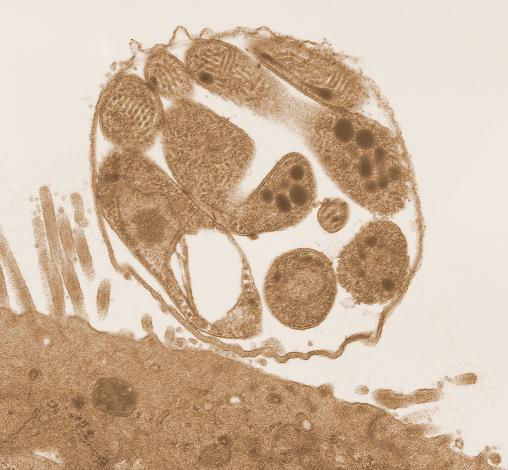

Huang等人的一项新研究发现了一种小隐孢子虫ABC转运蛋白,该转运蛋白对一种有毒的肠道微生物代谢物具有抗性。

A new study by Huang et al. identifies a Cryptosporidium parvum ABC transporter that confers resistance to a toxic gut microbial metabolite.